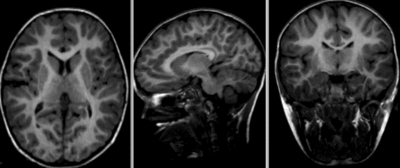

this is the fixed reference image. All images are aligned into this space lleft this is the moving image. The transform is calculated by matching this to the reference image

fixed image/target moving image

• reference/fixed : T1 SPGR , 1x1x1 mm voxel size, 256x256x192 ,sagittal

• moving: T1 SPGR , 1x1x1 mm voxel size, 256x256x192 ,sagittal